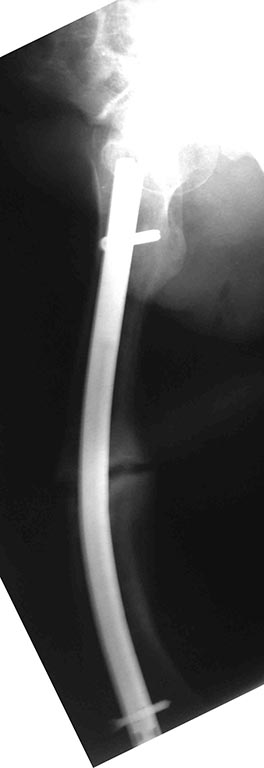

В травматологическом отелеении находится 16 летний юноша с

пателло-феморальным артрозом,

вторичной деформацией мыщелка бедра и надколенника.

Обратился с жалобами на боли в левом коленном суставе при ходьбе. В 2011

году находился на стационарном лечении в нашей кинике по поводу

застарелого перелома внутреннего края левого надколенника с разрывом

капсулы сустава, хондромаляции наружного мыщелка бедра и гемартроза. За

год до госпитализации перенёс двукратный спонтанный вывих левого

надколенника. В отделении (март 2011 года) выполнена артроскопия,

санация гиалинового хряща наружного мыщелка. Артропластика по Кемпбеллу.

При осмотре: Походка не изменена. Вальгусная деформация коленных

суставов: справа 12, слева 15. Движения в коленных суставах в полном

объёме. Выпот не определяется. Наружная ротация левой стопы 15-20

градусов. Левый надколенник латеролизован. При сгибании левого

коленного сустава происходит наружная дислокация надколенника. Фото

больного и результаты рентгенологического обследования прилагаем (будут

выкладываться последовательно).